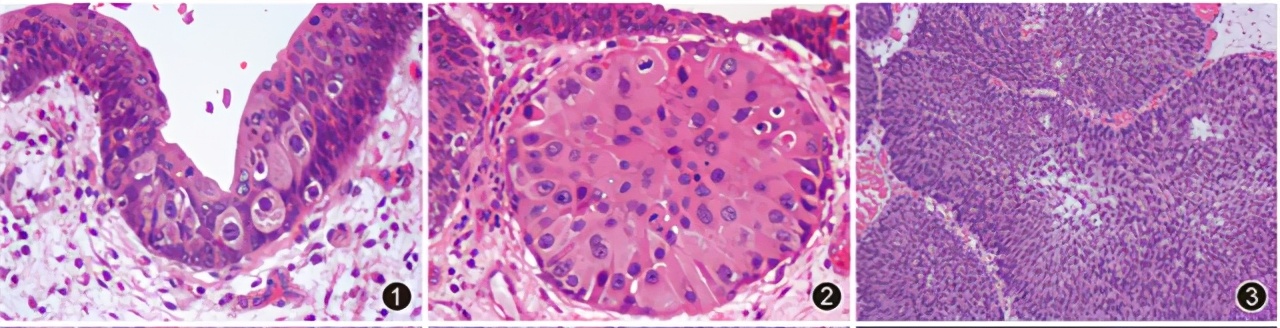

内镜检查及胃黏膜活检是慢性胃炎主要的医学检查 。医生会根据患者个体差异进行相关用药,对于大多数患者而言,慢性胃炎属于良性疾病,经过有效治疗完全是可以控制住的,但是部分患者会有一些这样的担心说萎缩性胃炎会不会导致癌变的可能吗?

一般来说 异型增生 亦或者称为上皮瘤变是胃癌 癌变前的病变 ,一般分为低级别和高级别两级病变之分。异型增生会随着年纪的不断变化会增加增生的概率。

慢性胃炎会有癌变的风险吗? 一般情况下慢性胃炎是不会发展成癌,但存在小概率的癌变可能性。